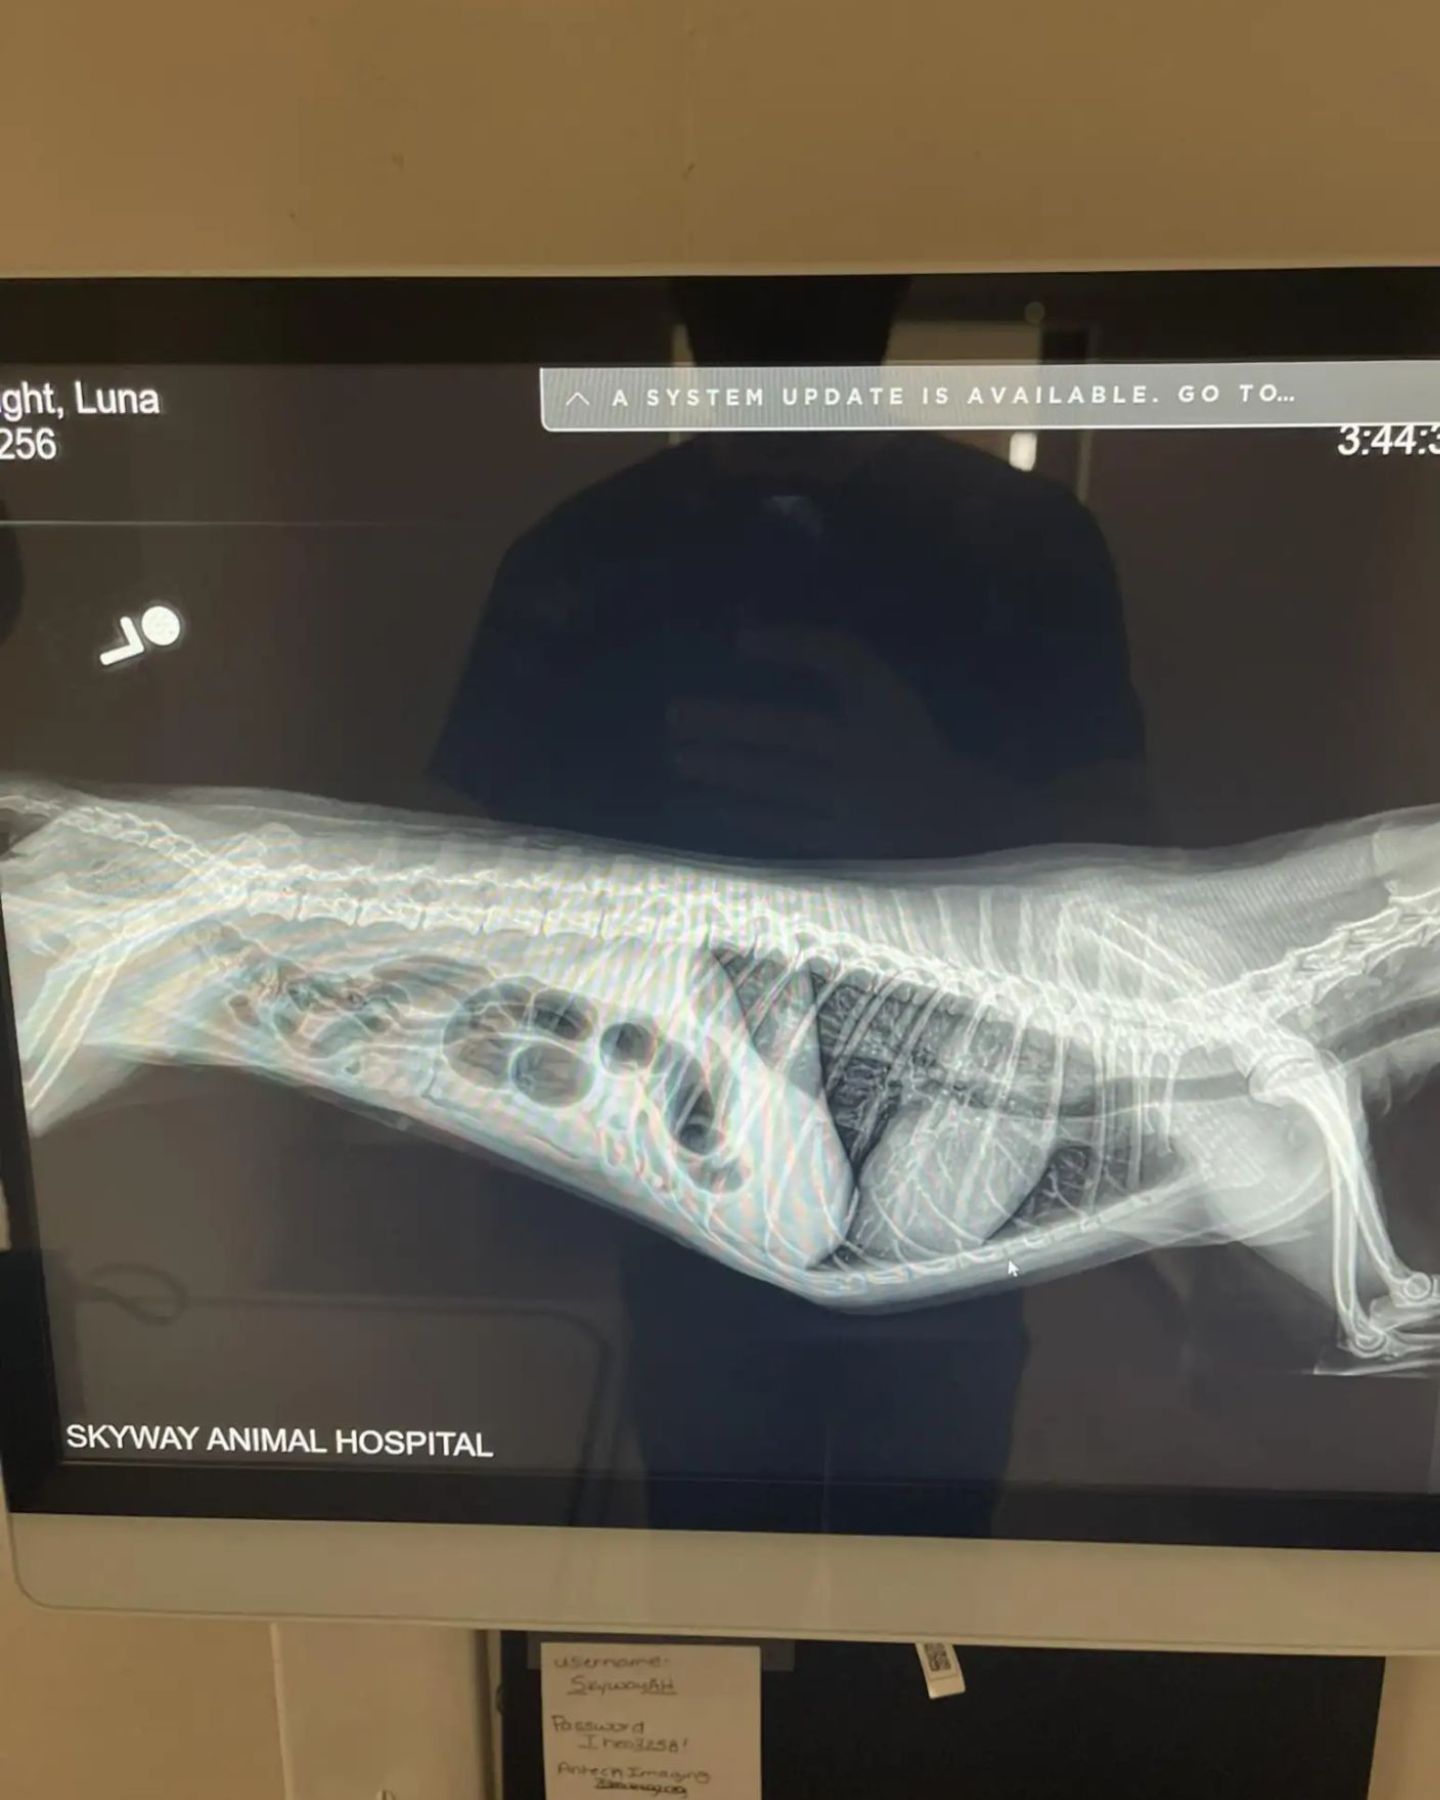

X-rays hinted at something deeper, yet there were no clear answers.

She thought Luna might have gotten to one of the fruits. But scans didn’t show a seed in her belly or throat. The mystery deepened.

It wasn’t until a special barium study was ordered that the truth finally appeared. The seed had been stuck in Luna’s throat the whole time, almost invisible, yet causing excruciating pain.